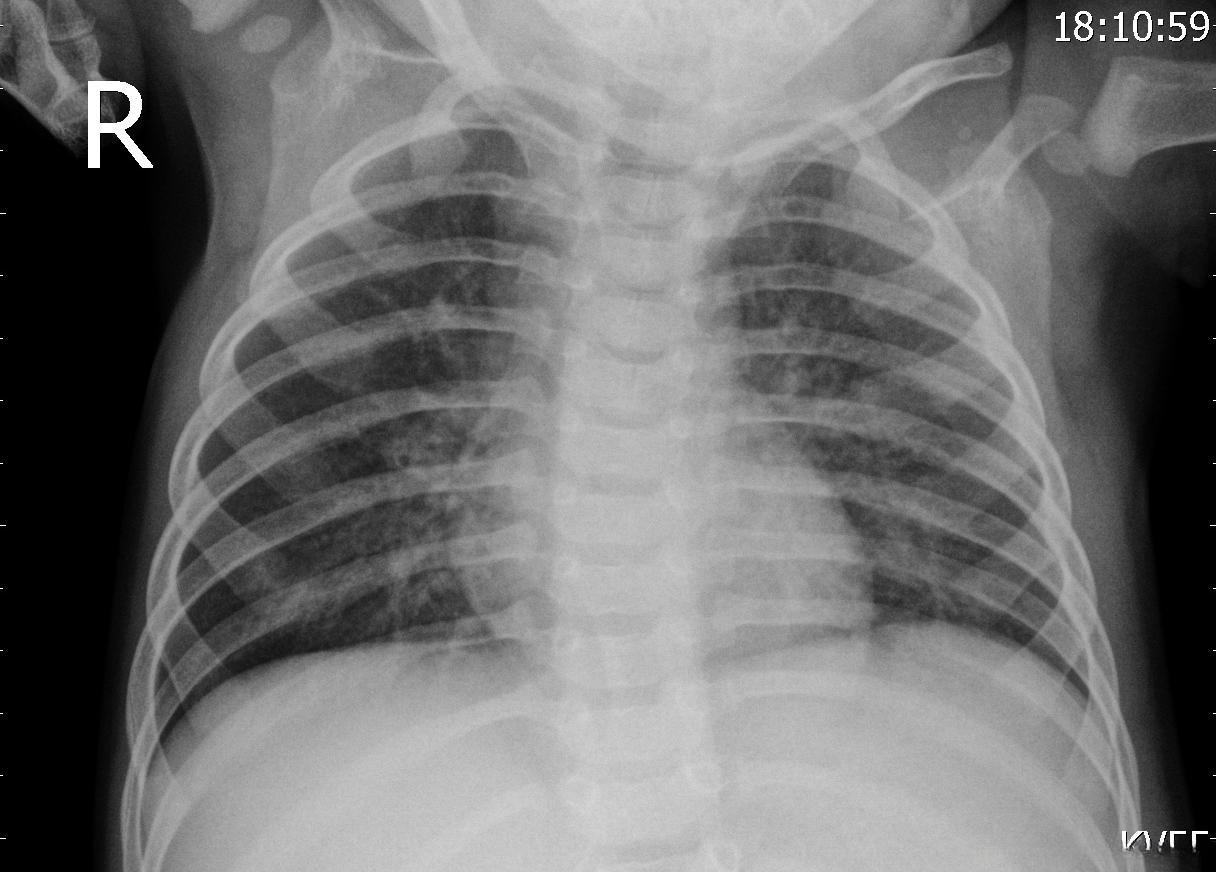

下面的是患有肺炎的X射线图

对于普通用户而言,在没有任何医疗背景的情况下难以准确判断是否患有肺炎。若采用基于CNN网络的图像分类方法,则能够在一定程度上降低医生诊断肺炎患者的劳动强度。